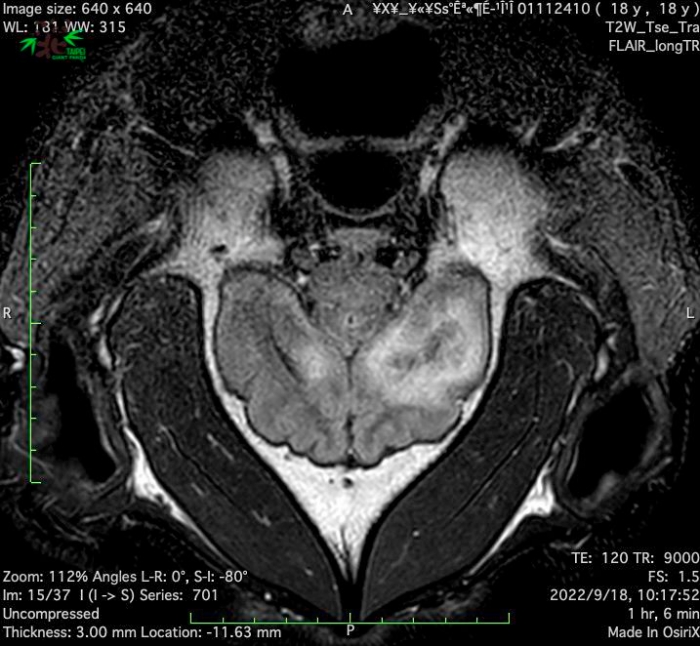

工作團隊回放監視器影像並針對團團進行觀察,畫面顯示在 8 月 23 日上午七點左右,團團發生了 3 分鐘疑似癲癇的症狀,獸醫師進行初步臨床檢查,並邀請臺大附設動物醫院神經專科獸醫師會診,認為團團有必要接受「腦部MRI(磁振造影)」精密檢查來釐清癲癇發生的原因,因此特別安排團團於 9 月 18 日到臺大附設動物醫院接受相關檢查!

9 月 18 日上午載著團團及工作人員的車隊抵達臺大附設動物醫院,隨後為團團麻醉、再進行腦部 MRI 檢查。MRI 影像顯示團團左大腦半球有局部液化壞死病變,右大腦半球亦可見類似病變,此病變可能是造成團團癲癇發作的原因。為進一步釐清腦部病變的可能肇因,獸醫師為團團採取腦脊髓液進行後續的分析化驗,也同時完成整體生理檢查。

近日團團在後場休養觀察中,後續須等待匯集所有檢驗結果才能釐清病因。這次為團團進行的MRI檢查,由動物園動物醫療照管團隊、臺大附設動物醫院獸醫神經專科張雅珮獸醫師及影像科余品奐獸醫師團隊,以及臺大醫院麻醉部黃啟祥醫師等共同完成任務,為大貓熊健康照護寫下歷史的新頁。